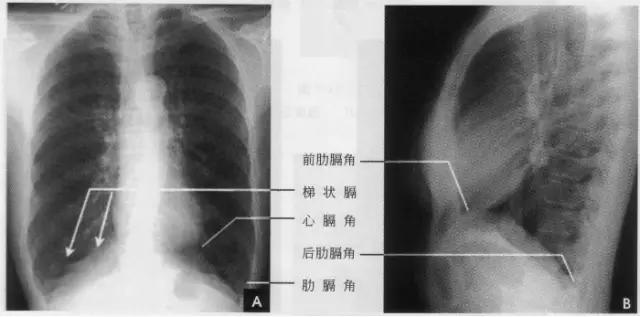

在正位胸片上,膈显示为圆顶状阴影,边缘光滑整齐,顶峰靠近中内1/3处。内侧与心脏形成心膈角。外侧与胸壁相交形成肋膈角;在侧位片上,圆顶部靠前,前端与前胸壁形成前肋膈角,后部与后胸壁形成后肋膈角,正常时前、后肋膈角均为锐角,后肋膈角位置最低。右膈顶的位置,一般与第6前肋或第10后肋等高,多数人右膈比左膈高1~2cm,这是因为心脏位置偏于胸腔左侧,故而将左膈压低。膈的位置在正常时可有若干变动:例如儿童膈位置较高,老年人则较低;矮胖型膈位置较高,瘦长型则较低;卧位时膈位置较高,立位时则较低;呼气时膈位置较高,吸气时则较低等。

膈形态的变异有:

①局限性瞒膨出:系蕊部分肌纤维短而薄弱引起张力不匀所致。

②波浪瞒:在深吸气时膈面呈3~4个小弧形隆起影,边缘部相互重叠。这是由于膈个别肌束肥大引起其收缩不均匀所致。

③梯状膈。深吸气时膈面出现数个呈梯状排列、尖端引向外上方的突起影,这是由于附着于各前肋端的膈面被肋骨过度牵引所致(如下图)。